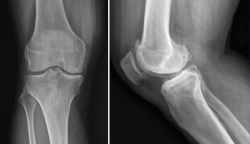

1.1.2. Tibia (Figura 2)

Figura 2. Radiografías anteroposterior y lateral de rodilla: fractura con varios trazos de meseta tibial externa.

1.1.3. Rótula (Figura 3)

Figura 3. Radiografías anteroposterior y lateral de rodilla: fractura del polo superior de la rótula.

1.2. Luxación femorotibial

La luxación traumática de rodilla es una entidad poco frecuente, que representa menos del 0,5% del total de las luxaciones articulares(3).

Requiere un tratamiento precoz, ya que una de sus complicaciones más graves es la lesión de la arteria poplítea, para cuyo diagnóstico se recomienda realizar un estudio de angio-TAC (Figura 4).

Figura 4. Radiografías anteroposterior y lateral de rodilla: luxación anterior de tibia y peroné.